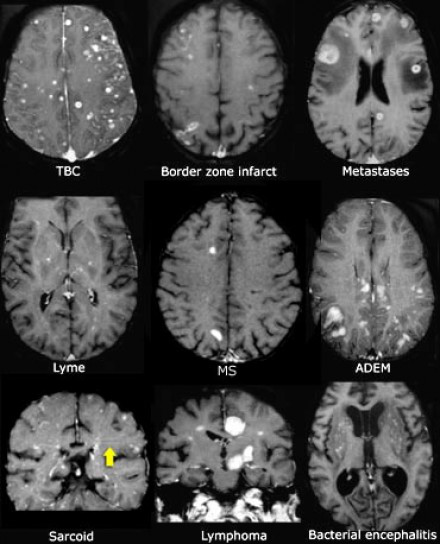

多發(fā)性增強病灶的鑒別診斷

圖片二

在上圖中,是各種多發(fā)性增強白質(zhì)病灶圖像,我們對其中部分病例進行詳細討論。需要說明的是,以下鑒別診斷中提到的疾病與上圖中的圖像并不完全重合。

血管炎

大多數(shù)血管炎性疾病的MRI成像特點是點狀增強。

腦部血管炎常見于系統(tǒng)性紅斑狼瘡、結(jié)節(jié)性多動脈炎(PAN)、白塞病(Behcet)、梅毒、韋格納肉芽腫(Wegener)、干燥綜合征(Sjogren)和原發(fā)性中樞神經(jīng)系統(tǒng)血管炎。

白塞病(Behcet)

白塞病更常見于土耳其患者。典型MRI表現(xiàn)是急性期出現(xiàn)腦干病灶結(jié)節(jié)性增強。

其他疾病的腦轉(zhuǎn)移病灶

其他疾病的腦轉(zhuǎn)移病灶周圍常包裹有水腫帶。

交界區(qū)腦梗死

周圍交界區(qū)腦梗死在病變早期可出現(xiàn)增強病灶。

血管周圍間隙